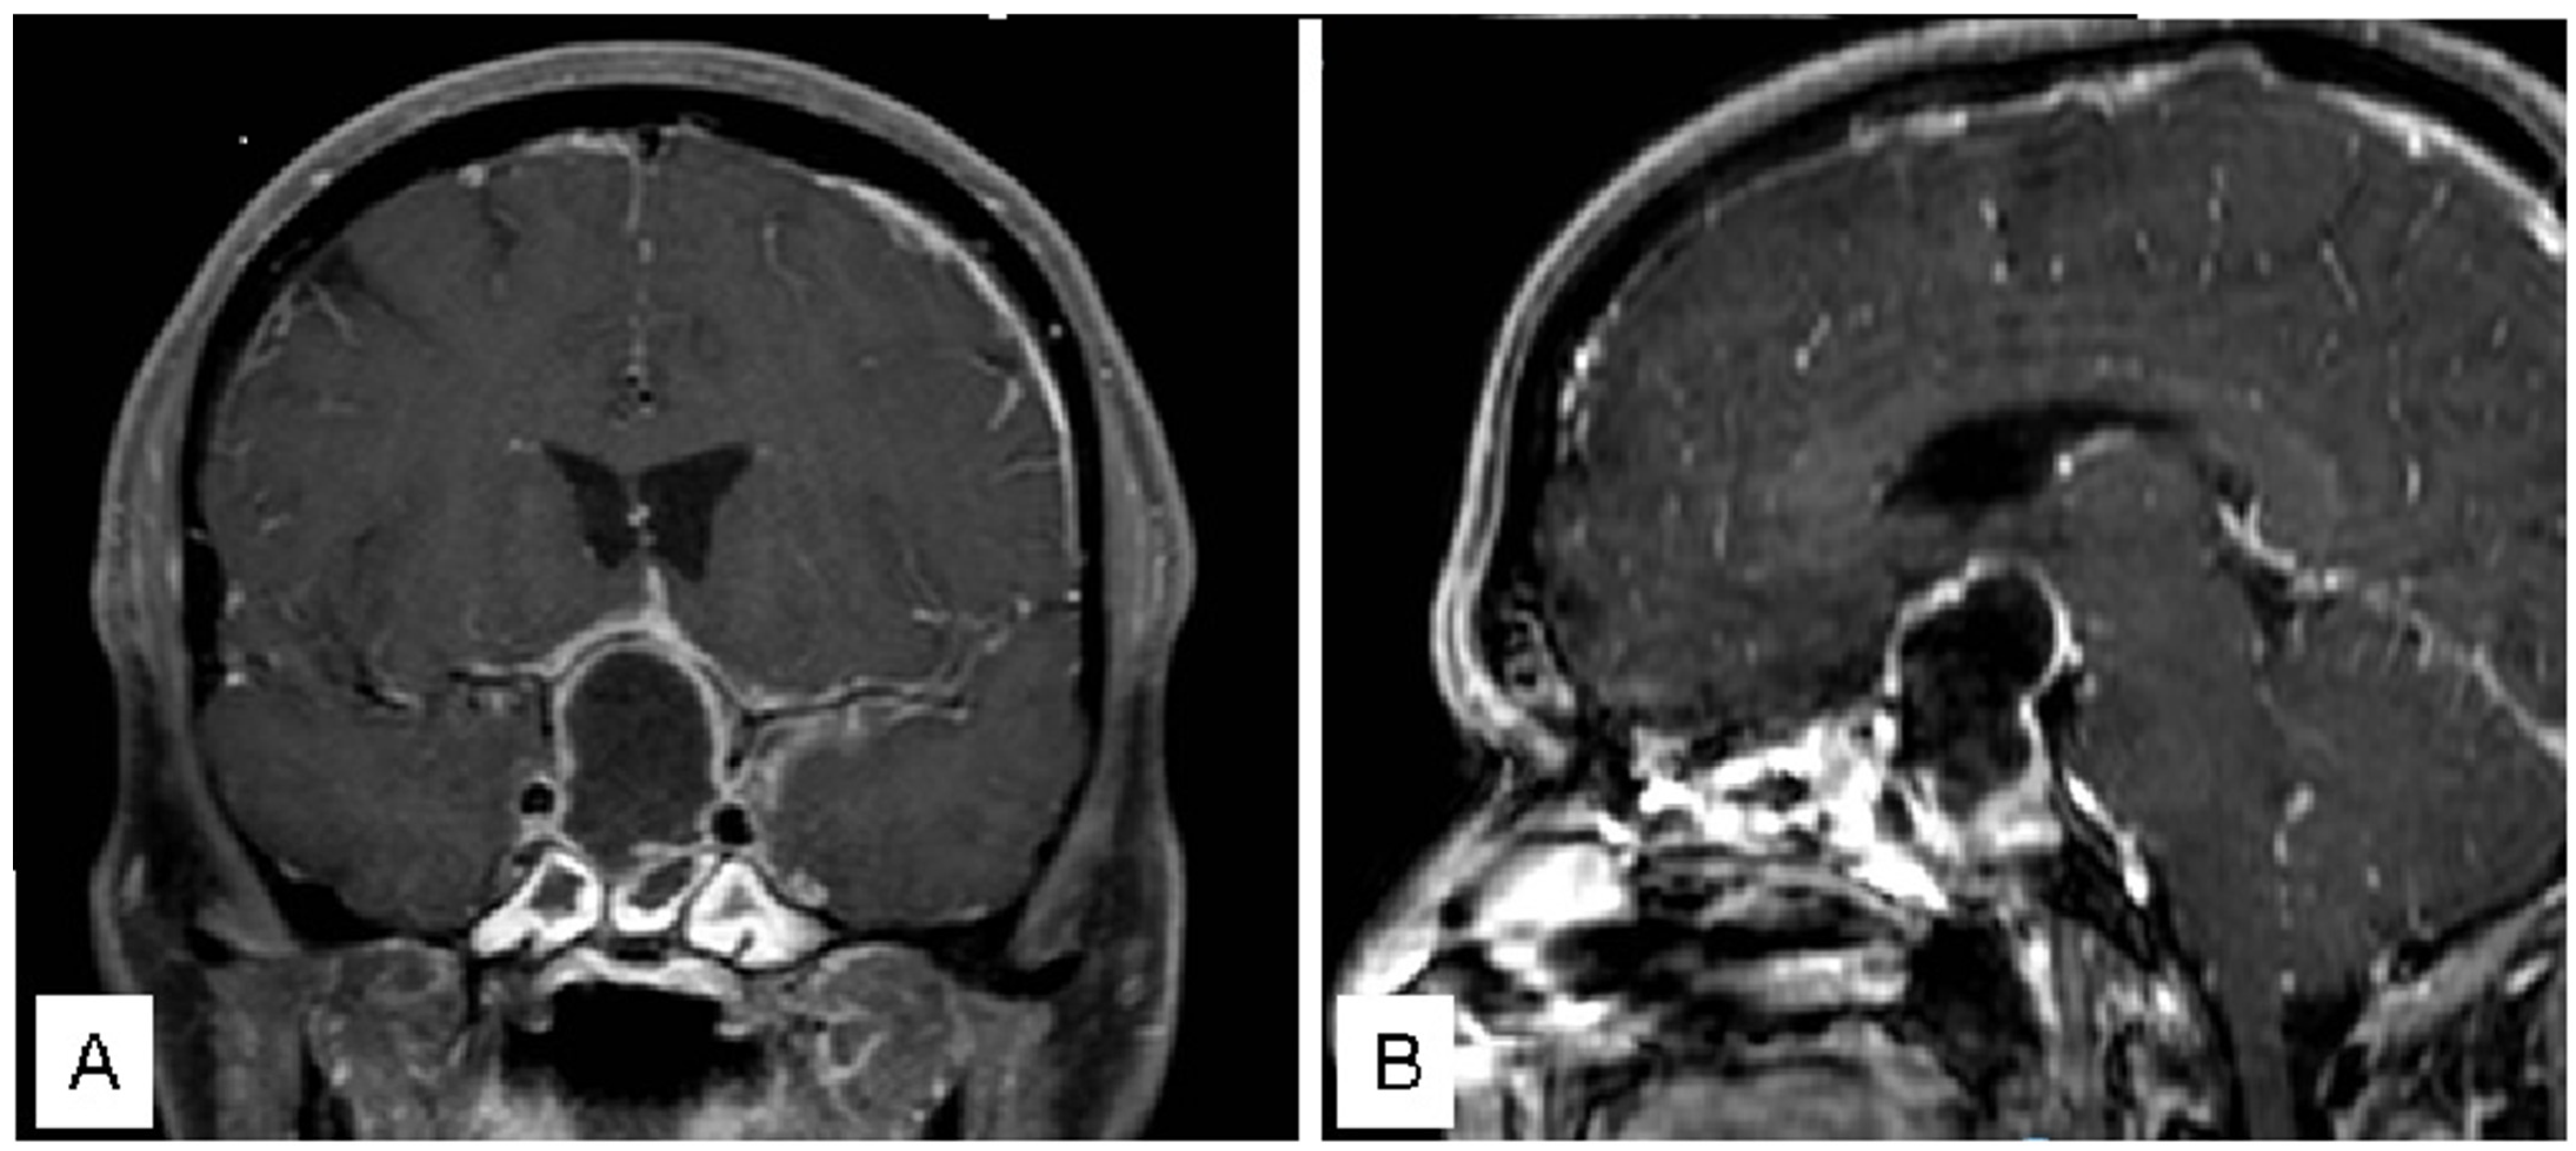

3.1.1. Case 1

3.1.2. Case 2